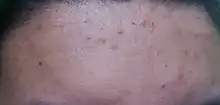

Miliaria rubra in a forehead

Symptoms of miliaria include small, red rashes, called papules, which are irritated and itchy. These may simultaneously occur at a number of areas on a patient's body, the most common including the upper chest, neck, elbow creases, under the breasts, and under the scrotum.[3] Other areas include skin folds and areas of the body that may rub against clothing, such as the back, chest, and stomach.